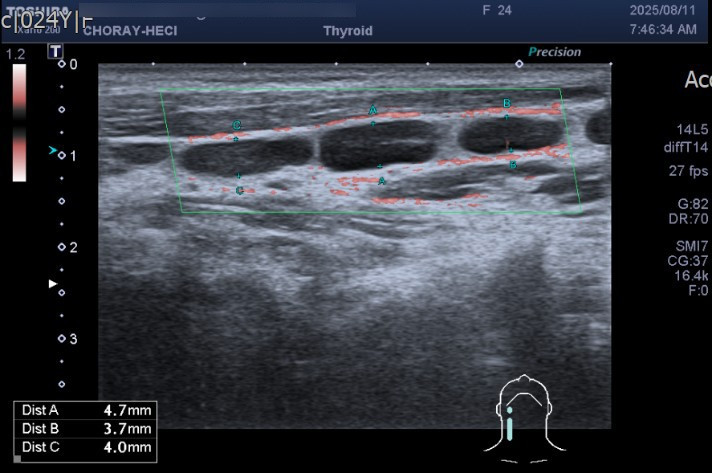

Nhiều hạch cổ hai bên - Ảnh BVCC